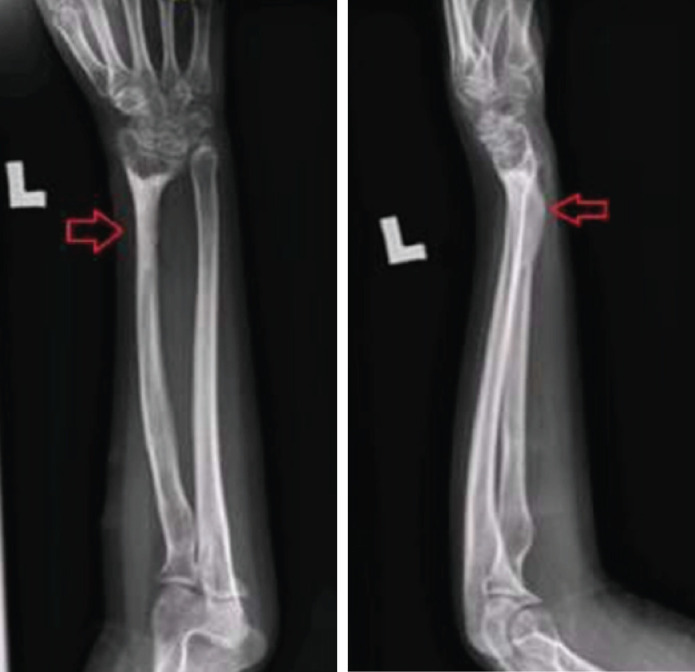

桡骨远端骨折是儿童前臂骨折中最常见的类型。肢体损伤最严重的后果是生长停滞,这可能导致畸形甚至肢体长度的显著差异。因此,我们想和大家分享我们治疗一位在事故中身体受伤后左桡骨停止生长的病人的经验。案例介绍:我们遇到了一个10岁的女孩,她卷入了一场道路交通事故。患者左侧桡骨远端持续闭合性骨折(Salter Harris 2)。患者晚期求医,采取破骨术、切开复位、左桡骨k线固定骨折,但骨愈合后左侧桡骨生长停止。据观察,她的左桡骨比右桡骨短约4厘米。她做了左桡骨截骨手术并植入了LRS。术后6个月后,她的左上肢没有明显缩短,桡骨长了大约4厘米。左桡骨延长后无神经血管损伤。手术一年后,病人说她的左上肢没有任何不适。尽管ilizarov方法很流行,单轨外固定架,也被称为LRS,是桡骨延长的一种选择。在我们的情况下使用了LRS,结果证明了它的有用性。

Fractures of the distal radius are the most common type of forearm fractures seen in children. The most serious outcome of physeal injuries is growth arrest, which can result in deformity and even significant differences in limb length. Therefore, we'd like to share our experience with treating a patient whose left radius stopped growing after she had a physeal injury in an accident. Case presentation: we encountered a 10-year-old girl, who was involved in a road traffic accident. She sustained closed fracture distal end left radius (Salter Harris 2). She sought medical assistance late, so osteoclasis, open reduction, and a k-wire on her left radius to fix the fracture, however it was complicated with growth arrest of left radius after the bone united. It was observed that her left radius was around 4cm shorter than her right. She had an osteotomy performed on her left radius and a LRS implanted. After six months post-surgery, there was no visible shortening of her left upper limb, and the radius had grown by around 4cm. There was no neurovascular impairment after left radius lengthening. After a year had passed after her operation, the patient said she had no complaints about her left upper limb. Despite the prevalence of the ilizarov method, the monorail external fixator, also known as LRS, is an option for bone lengthening of the radius. The LRS was utilised in our situation, and the results demonstrated its usefulness.